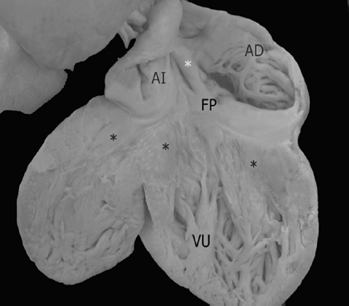

Los 2 corazones formaron parte de un situs solitus auricular, ambos con doble entrada a ventrículo único a través de una válvula auriculoventricular común cuyas valvas estuvieron adosadas a la pared ventricular; las grandes arterias normalmente relacionadas emergieron del ventrículo único con estenosis pulmonar infundibular y valvular (Fig. 5); el adosamiento y desplazamiento valvares cubrieron toda la porción de entrada y la zona trabecular posterior hasta la región apical con una gran auricularización del ventrículo único; estuvieron ausentes las cuerdas tendinosas y los músculos papilares (Fig. 6); la porción funcional efectiva del ventrículo se redujo a la zona trabecular anterior y a la región infundibular (Fig. 5). En el segundo corazón las grandes arterias estuvieron también normalmente relacionadas pero con dilatación y ambas emergieron del ventrículo único (Fig. 7). El adosamiento y desplazamiento valvares estuvieron reducidos a la porción proximal de la válvula por lo que la auricularización fue menor y mayor la porción funcional del ventrículo único (Fig. 8). Ambos corazones tuvieron un tabique interauricular pequeño con foramen primum (Tabla 1).

Figura 6 Vista interna posterior del corazón de la Figura 5. Obsérvese las aurículas en situs solitus conectadas con el ventrículo único, las valvas de la válvula auriculoventricular adosadas a las paredes de esta cámara ventricular (3 asteriscos negros) desde la unión auriculoventricular hasta la región trabecular apical, el tabique interauricular rudimentario y un foramen primum. AD: aurícula derecha; AI: aurícula izquierda; FP: foramen primum; VU: ventrículo único.